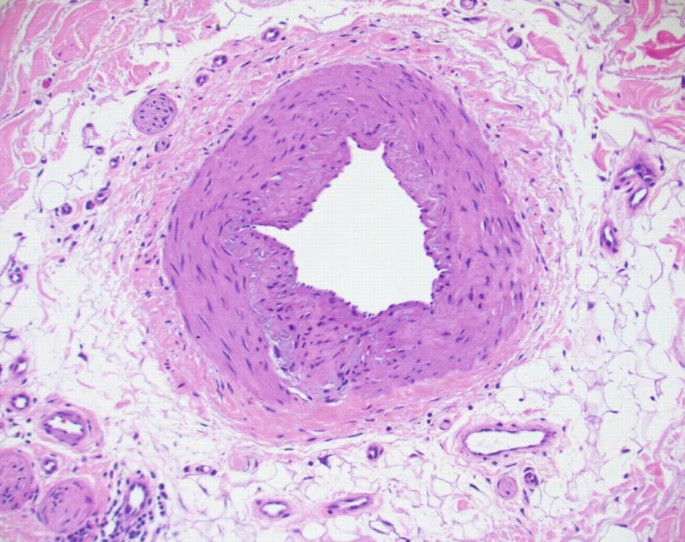

The composition of the epidermis dermis and subcutaneous fat is reviewed in great detail. This chapter discusses the structure histology and function of the skin. Practice all cards Apocrine glands Coiled structures attached to hair follicles found in.

Appendages of the skin include.